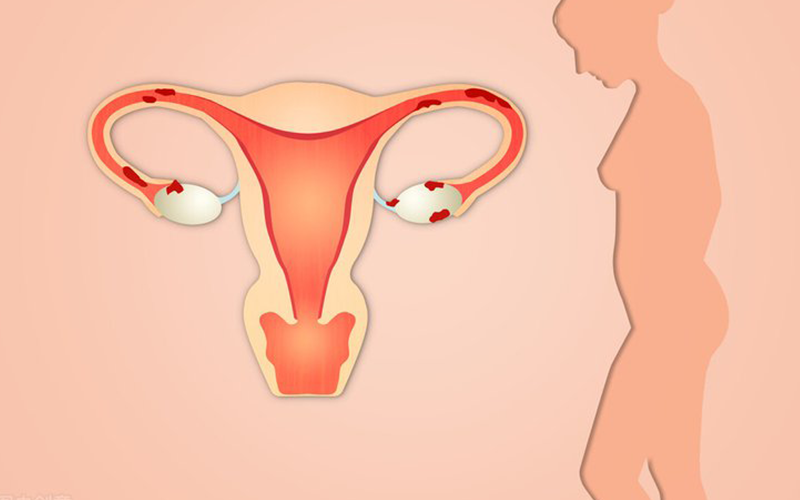

一般优先建议选择移植鲜胚的原因主要是由于鲜胚的胚胎活性强,试管的成功率比较高。其实鲜胚移植的成功率还是...

超过45岁的女性做试管婴儿成功率大概只有10%左右,并且做试管一次成功率特别的小,因为随着年龄的增长,...

江西省妇幼保健院三代试管的费用一整套流程下来差不多价格在4万元左右,他们的所有费用价格明细全部都会通过...

目前,在中南大学湘雅医院做试管婴儿的试管婴儿医院费用大概在5-12万元左右。费用内容包括:检查费用、药...

34岁做7次试管婴儿都没成功可能是因为年龄或者多方面原因造成的,比如女性的子宫坏境差试管婴儿,医生的试...

三代试管包生男孩的费用没有一个具体的数字,花费多少因人而异 ,不同的医院收费不同,便宜的也有五六万的,...

国内没有一家试管婴儿医院可以包成功,不管试管技术有多么先进,医生有多么厉害,也不可能百分之百成功,某些...

去私人医院做试管是不可以选择男孩的,目前国内不允许试管选性别,除非父母双方有生女儿必然有缺陷的的基因,...